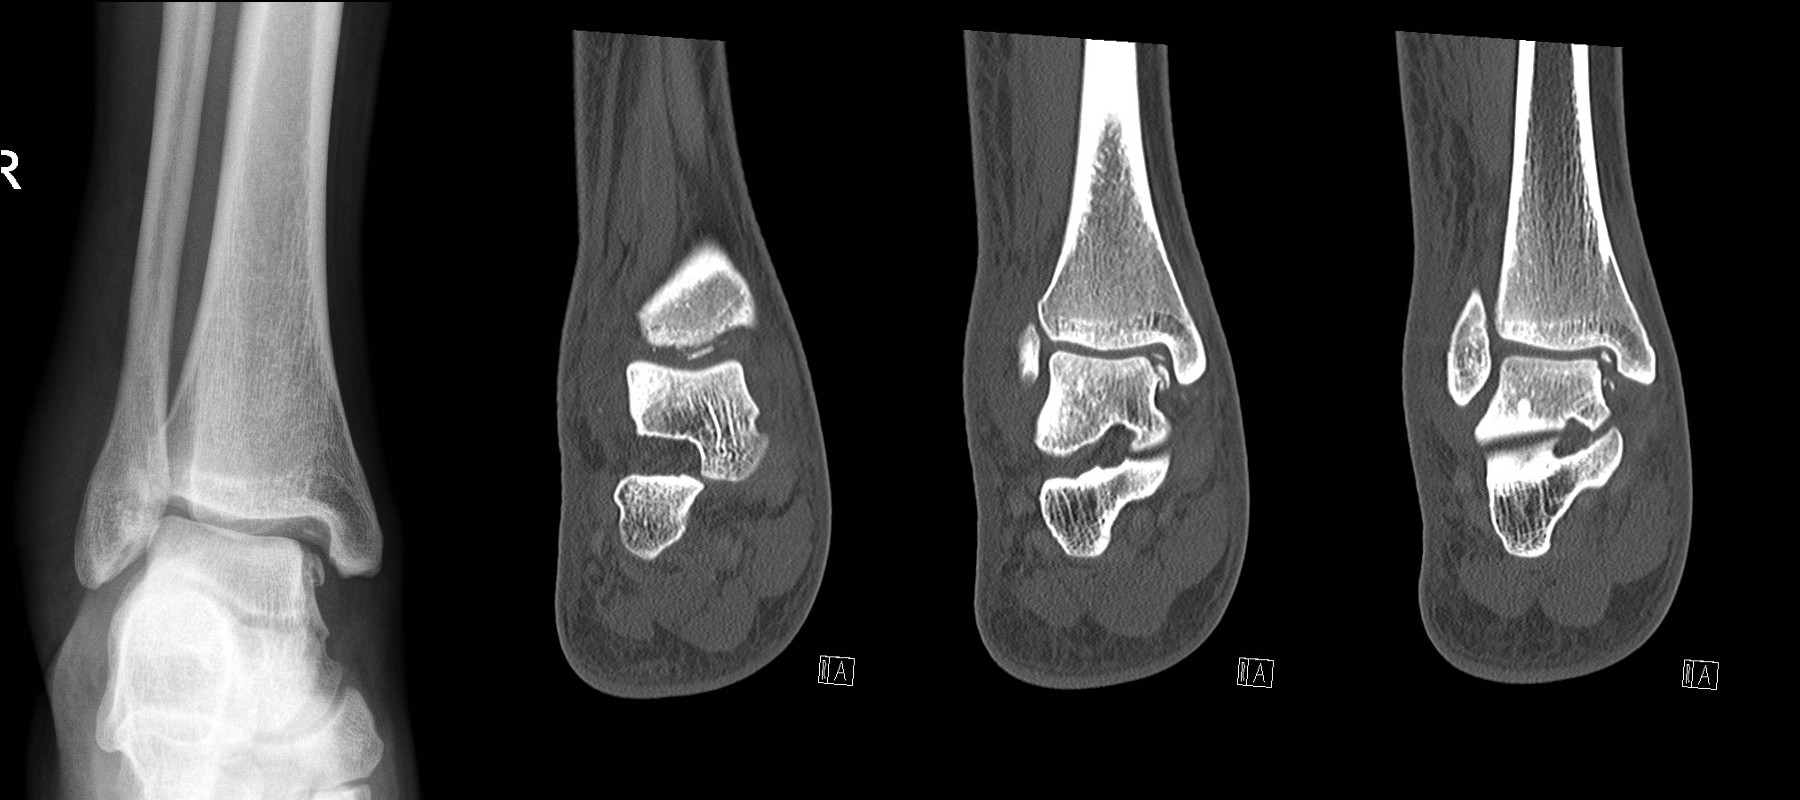

Intra-articular calcaneal fractures

- Refer to the Orthopaedic team

Talar dome fracture – looks simple on plain X-ray but CT shows multiple intra-articular bony fragments.